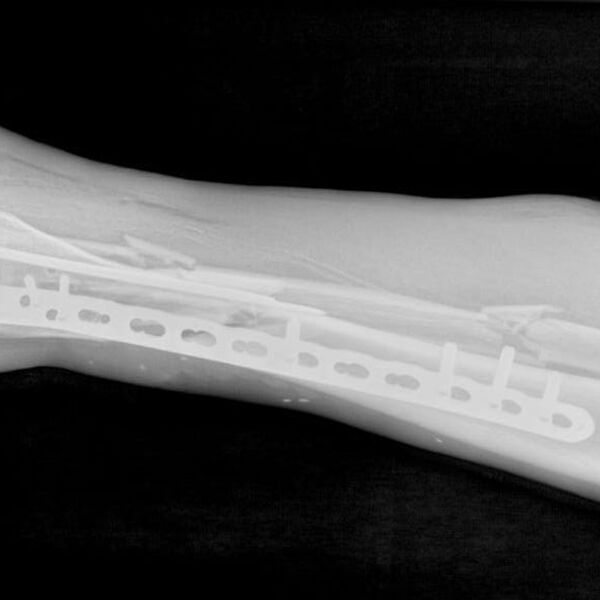

У пострадавшего были диагностированы перелом костей правой голени со смещением, рваная рана бедра и обширная рана левой голени. В больницу мужчину доставили вместе с плугом культиватора. На момент поступления нога была холодной и посиневшей, кровь в конечность не поступала.

«Мы провели срочную операцию, в ходе которой промыли раны и закрепили отломки костей правой голени в анатомически правильном положении с помощью аппарата внешней фиксации. Также восстановили кровоток и устранили сдавление сосудов», — рассказал врач-травматолог-ортопед Игорь Кучерявый.